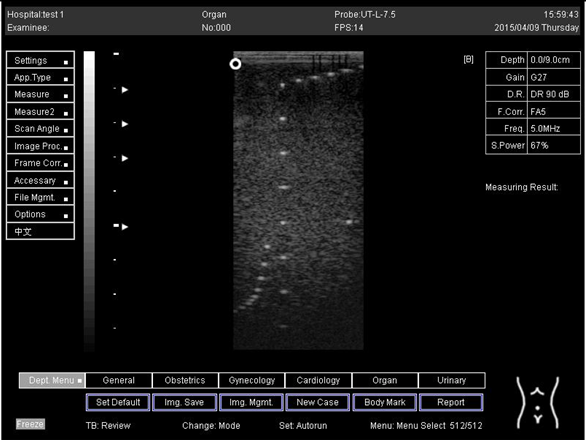

9.0 Axial resolution

Biomimetics 07 00130 i001

D1 = 4.9

D2 = 4.1

D3 = 3.1

D4 = 2.2

Lateral resolution

Biomimetics 07 00130 i002

D1 = 5.0

D2 = 4.0

D3 = 3.0